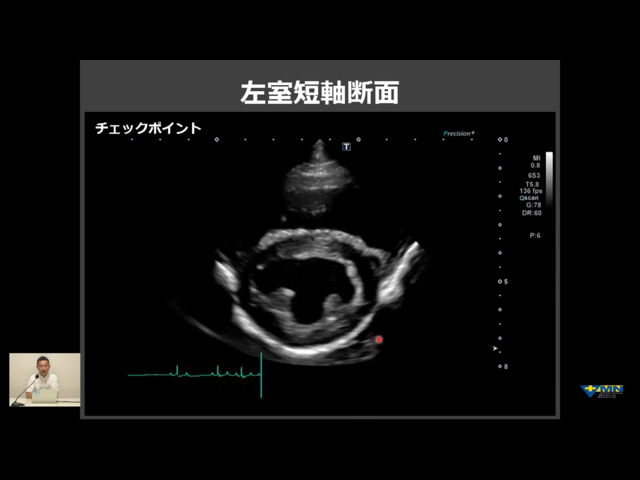

・左室短軸断面の描出法 (動画あり)

・異常所見があった時の基本的な考え方 - ・左室短軸断面 (動画あり)

・遠心性肥大 (動画あり)

・遠心性肥大の鑑別 (動画あり)

・求心性肥大 (動画あり)

・求心性肥大の鑑別

・右心系の評価 (動画あり) - ・心基底部短軸断面 (動画あり)